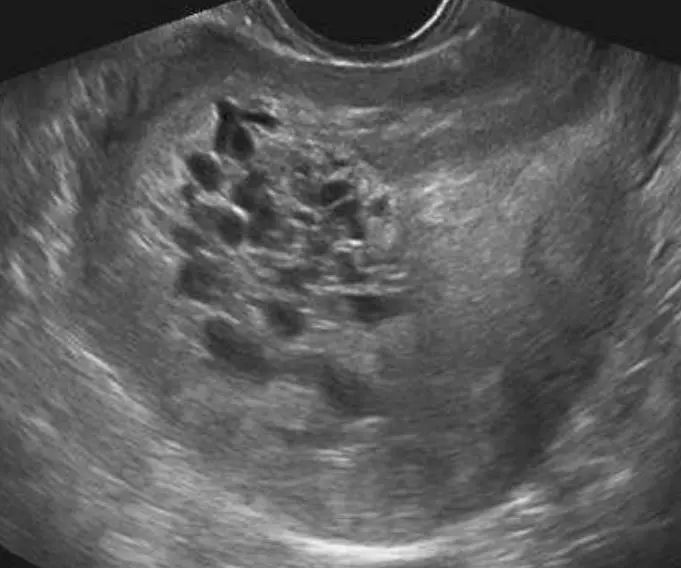

医生说,琴琴这种情况是属于葡萄胎,是受精卵异常导致的。如今只剩下一些长得像葡萄和小蝌蚪一样的细胞。如果在50天左右做产检是可以检查出来的。但是琴琴这几个月来一直没有做检查,胎儿早就死亡了。

而琴琴自己能活到现在已经非常幸运了。因为葡萄胎不仅会让胎儿百分百死亡,对孕妇的生命也有威胁。葡萄胎在孕妇体内的时间越长,孕妇就越危险。